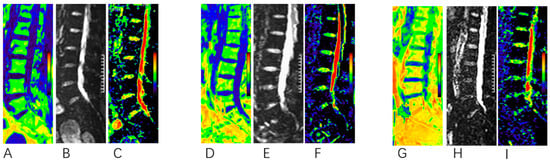

2.4. MR Examination

2.5. Image Analysis